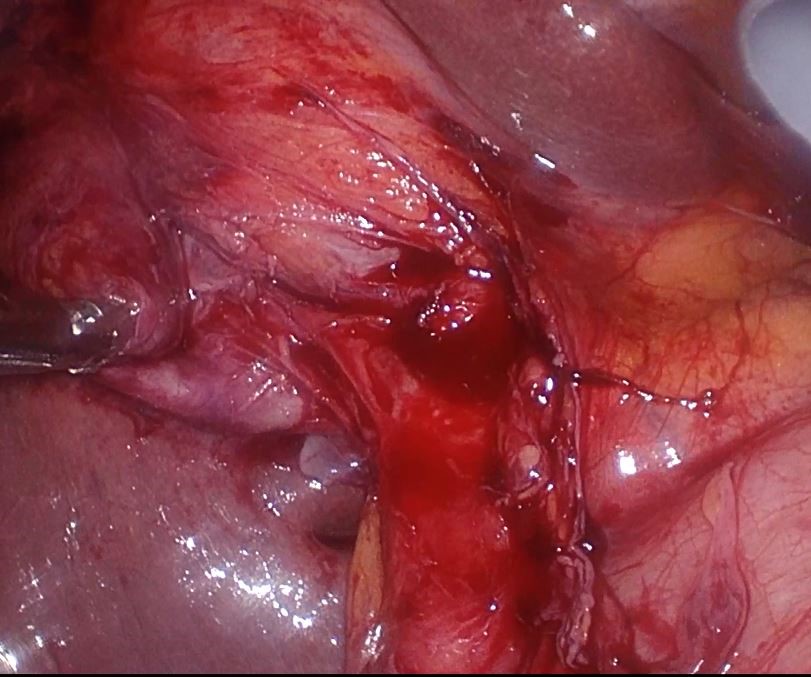

Abdominal ultrasound (US) showed a thickened wall of gallbladder and the lithiasic cholecystitis in GB which rolled around itself. She was further investigated with Magnetic resonance cholangio pancreatography (MRCP), which confirmed the cholecystitis on GB which rolled around itself and revealed normal CBD (Figure 1). A decision was made to procedure with a laparoscopic cholecystectomy. Intaoperatively two gallbladders enveloped in a single peritoneal membrane and two cystic duct was observed (Figure 2). It was an operative suprize because her MRCP did not reveal any evidence of duplication of the gallbladder. Intaroperative cholangiography was decided to identify the biliary tree. This cholangiogram confirmed the presence of two cystic ducts opening in the CBD (Figure 3). After ligature of two separate cystic duct a challenging laparoscopic cholecystectomy was performed successfully.

Figure 2 . Intraoperative image showind two gallbladers